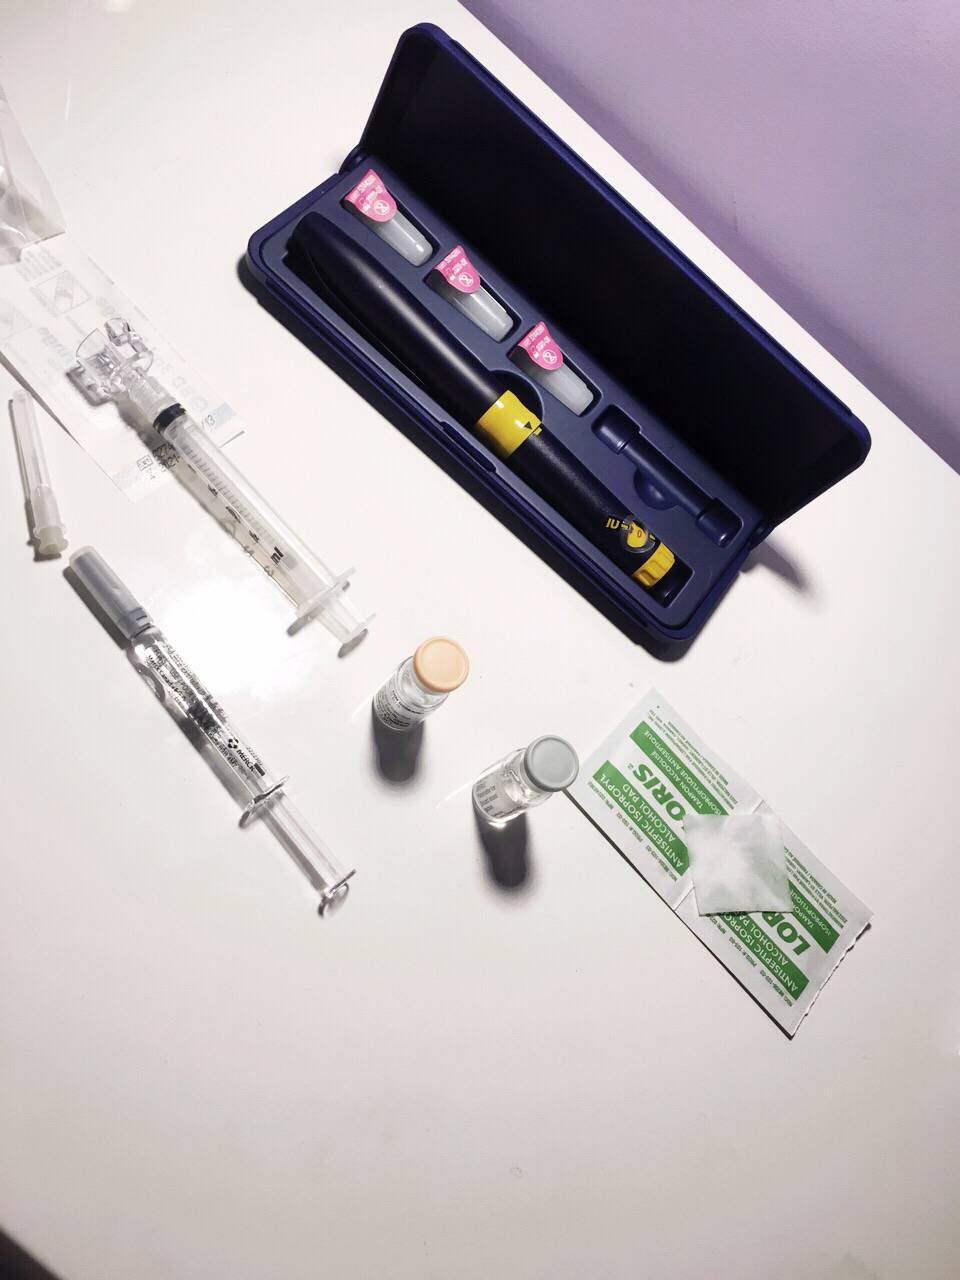

本人女29未婚未育手术前偶尔知道可以冷冻卵子 前提是要在化疗前做大家都知道化疗药物复合卵巢子宫都有一定副作用。一般医生都是建议内分泌药吃五年才可以考虑生孩子 生完继续内分泌五年我自己认为越年轻卵子质量也越好 数量可能也会相对高一点当我五年后34岁 我的卵子还是29岁的状态 而且是未受化疗药物污染的。我觉得为什么不尝试呢以下就来亲说我的取卵过程第一次去咨询的时候做了阴超显示可能有15颗左右卵子第二次是月经来的第二天 又检测了一下卵子 查了血接着自己回家打menopur 75IU ➕ purogan 225IU 每天还要吃一颗来曲挫到第五天的时候去诊所验血 下午通知加打一针orgalutran 接下来的10天左右都是每天定点自己在肚子上打三针 最后五天开始每天检测卵泡大小是否超过17mm到了周一终于不用再打针了 因为周二可以取卵了我没有做全麻 首先做椅子上吃了止痛药 放松的药 还有打了头孢。时间差不多就走去手术室 准备手术术前医生先帮忙清洗下体感觉跟生孩子差不多的姿势 也不知道他弄了些什么 不痛 就是这时候开始打麻药了 有点晕接着正式开始手术 就看到屏幕里一根针插入卵泡把它慢慢吸走 接着换另一个卵泡接着吸一共吸了十分钟 就被告知手术结束了腿上轮椅回到休息室休息了一个小时 并且打了点滴 才让我不那么晕也不想吐了 回家接到电话 取出22枚卵子。成熟的可以冷冻的有9颗好吧虽然一残都没到。但我多了一条后路哪天想生孩子 至少我还有年轻且健康的卵子存在想想心里也舒服点不是么附上我这两周自己给自己打的针 还有最后那些黑黑的球球就是卵泡😁